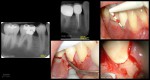

Probably not. When the CBCT shows the defect all on the buccal, I tend to go into hero mode….Today, I do what the patient tells me to do. I have a whole series of these now that we are monitoring. So far, I can’t think of a single one that suggests it is advancing. Maybe just dumb luck or no cats….